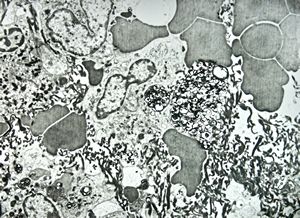

M,58y. | spleen - thesaurismosis of unknown origin … postmedicamentous?

M,44y. | spleen - Gaucher disease